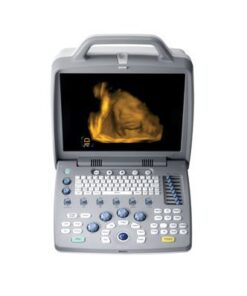

Portable Led Screen Ultrasound

XF300 (LED) B ultrasound diagnose medical instrument

Portable LED screen ultrasound

XF300 (LED) B ultrasound diagnose medical instrument

The fully digital ultrasound image diagnostic equipment,

12in LCD screen main unit with one probe |